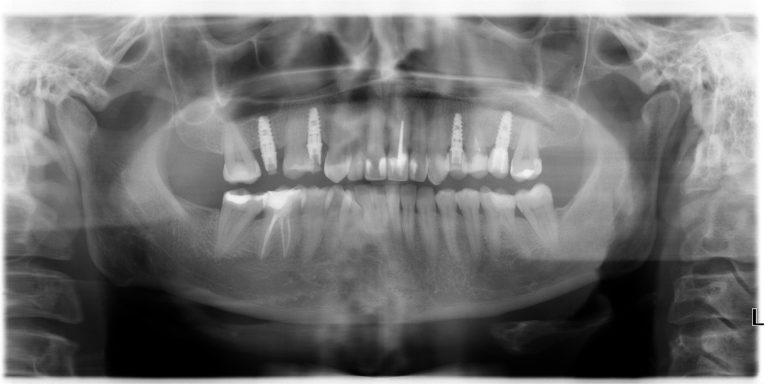

- выполнение компьютерной томографии и ортопантомограммы;

У меня дважды произошел отказ имплантов Alpha Bio, и второй раз установка была выполнена бесплатно. Возможно, дело было в неправильном размере или составе материала, но воспаление вокруг штифта начиналось сразу после установки. Я решил больше не связываться с этой клиникой и обратился в другую, более авторитетную. В первый день мне сделали панорамный снимок и порекомендовали установить импланты Astra Tech двухфазным методом. На этот раз все прошло успешно, и сейчас я готовлюсь к установке металлокерамической коронки.